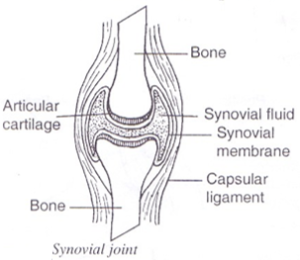

They are also called synovial joints because the joint area is filled with synovial fluid that lubricates the joint preventing friction between articulating bones.

Functions of some parts of a synovial joint

(a) Synovial membrane

- Surrounds the synovial cavity.

- Secretes the synovial fluid.

(b) Synovial fluid

- Lubricates the end surfaces of articulating bones hence reduces friction.

(c) Ligaments

- Hold articulating bones together.

(d) Articular cartilage

- Reduce friction between bones.

- Absorbs shock